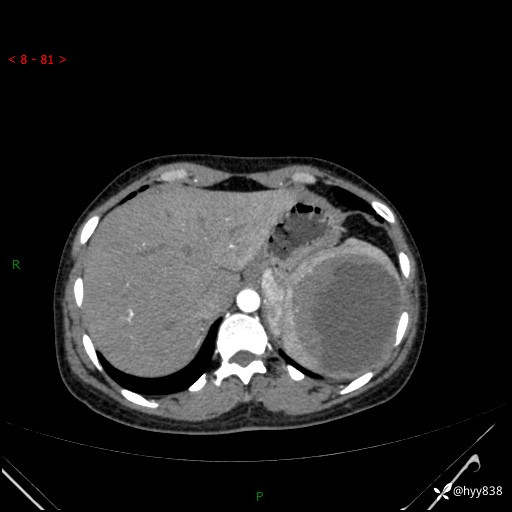

患者性别:男

患者年龄:44岁

主诉:外院超声发现脾脏占位,来我院进一步诊治。

辅助检查:CT

临床诊断:脾脏占位

脾脏CT平扫+增强(动脉期+静脉期)